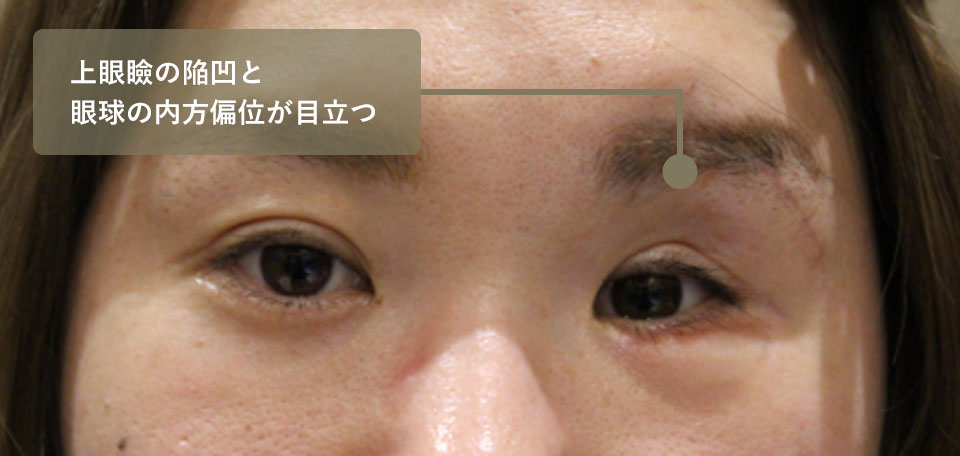

約20歳女性・転落事故

自宅マンション5階から転落、顔面多発骨折にてB大学病院形成外科で整復手術。半年後に眼窩骨折整復術と下眼瞼の陥凹に対して脂肪移植を施行しています。

左眼球陥凹が治らず浜松のC病院、群馬県のD病院を受診するが手術を断られ、最終的にD病院から当院へ紹介受診となりました。

B大学病院で2回手術をされていますが、左眼の重度の眼球陥凹が残存しており、左右非対称の顔貌となってしまっています。また下眼瞼へなぜか脂肪移植されているためこれも左右差を助長する原因となっています。